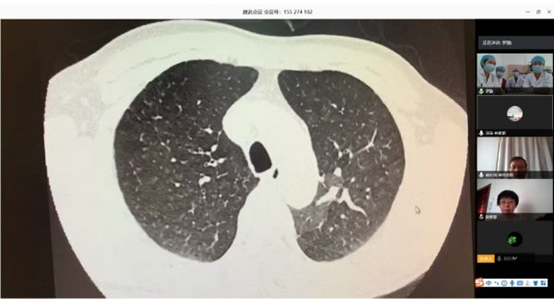

根據(jù)衛(wèi)健委新冠肺炎疫情防控工作總體部署以及醫(yī)院要求, 3月16日,北阜肺血管與血栓一病區(qū)和深阜肺血管病房已同步開(kāi)始有序收治患者,開(kāi)展包括右心導(dǎo)管、肺動(dòng)脈造影及慢性血栓栓塞性肺動(dòng)脈高壓患者的肺動(dòng)脈球囊擴(kuò)張術(shù)等手術(shù)在內(nèi)的肺血管病所有診治。為減少新冠肺炎疫情傳播風(fēng)險(xiǎn),保證深圳肺動(dòng)脈高壓患者得到最佳診療方案,北阜和深阜兩地肺血管病房充分利用“互聯(lián)網(wǎng)+醫(yī)療”的優(yōu)勢(shì)作用,開(kāi)展遠(yuǎn)程線上查房,對(duì)每位患者資料進(jìn)行詳細(xì)分析,確定診治方案,使深圳的患者在疫情特殊時(shí)期可得到與平時(shí)同樣的醫(yī)療服務(wù)。